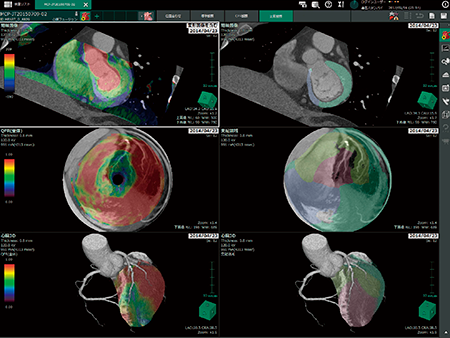

■4Dフロー(MRI)

食生活の変化,遺伝的要因などにより発症する高血圧症は,体幹部の大血管などで大動脈瘤,大動脈解離など重大な疾患を引き起こす。近年では,MR画像から血流速度,および血流方向を画像化し,これらの疾患を予測するといった研究も発表されている2)。

VINCENT V5で新規解析アプリケーションとして販売する“4Dフロー”では,MRIで3軸(xyz軸)方向ごとの3D cine phase contrast画像を収集し,画素値情報などから流速ベクトル,流線表示など,さまざまな血流情報を画像化(図3)できるようになっている。

図3 4Dフローの解析画像

4Dフロー用に撮影されたデータを時間軸方向で再生した流線表示画像例。アプリケーション画面上では➡の方向に再生しながら血流の流れ,速度などを観察できる。